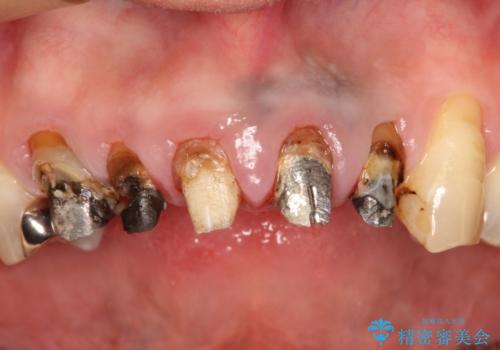

上の前歯の根元が黒い 根の治療を含めたセラミック再治療

- 上の前歯の根元が黒くなっているので、再治療をしたいとのことで来院された患者様です。

レントゲンを撮影すると、適合不良のかぶせ物が装着されており、根の治療も不十分であることが確認されました。

適合不良のかぶせ物をすべて除去して、根の中の治療から再治療を行うこととなりました。

適合不良のかぶせ物が装着されていた歯は、内部がやはり虫歯になっていました。

かぶせ物だけではなく見えないところも、精密な治療をすることが重要となります。